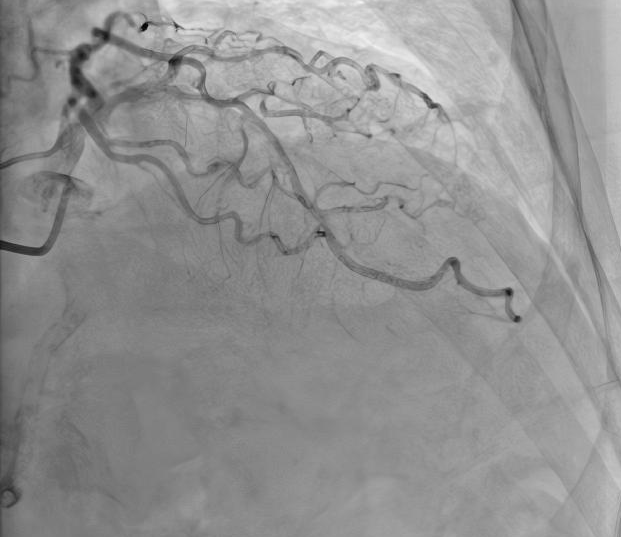

术前造影